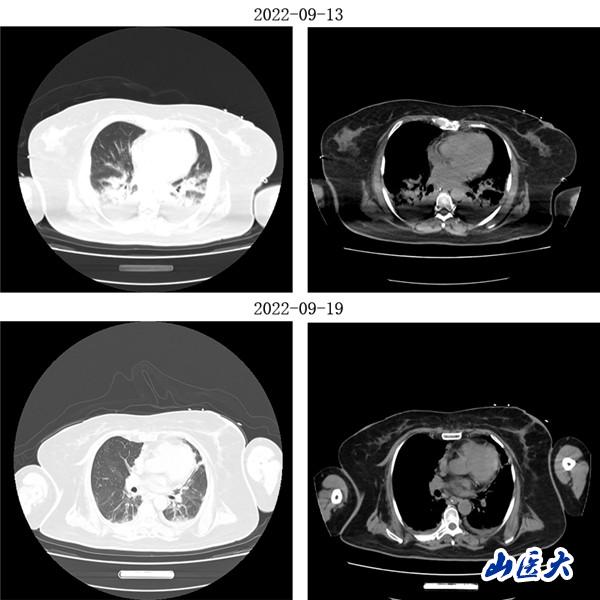

重症医学科三病区张文凯主任团队深入分析了两位患者的病情。考虑到两名老年患者均已出现急性呼吸窘迫综合征,决定采用俯卧位通气技术为他们治疗。在张文凯主任的指导下,侯林义主治医师带领张承、孙洁住院医师对女性患者经俯卧位通气治疗,92小时后复查胸部CT,双肺明显好转,氧合指数由90上升至300mmHg以上,吸氧浓度由100%降至35%,ARDS明显改善;对男性患者,采用联合持续性血液滤过(CRRT)治疗方案,经俯卧位通气治疗66小时后复查胸部CT,显示明显改善,同时氧合指数由102上升至360mmHg左右,吸氧浓度需求下降至40%,全身水肿情况也明显减退。

(男性患者治疗前后胸部CT对比)